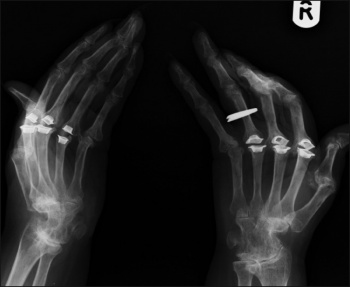

X-ray clearly showing joint replacements of the MCP joints secondary to deformities of inflammatory joint disease

X-ray clearly showing joint replacements of the MCP joints secondary to deformities of inflammatory joint disease(click to enlarge)